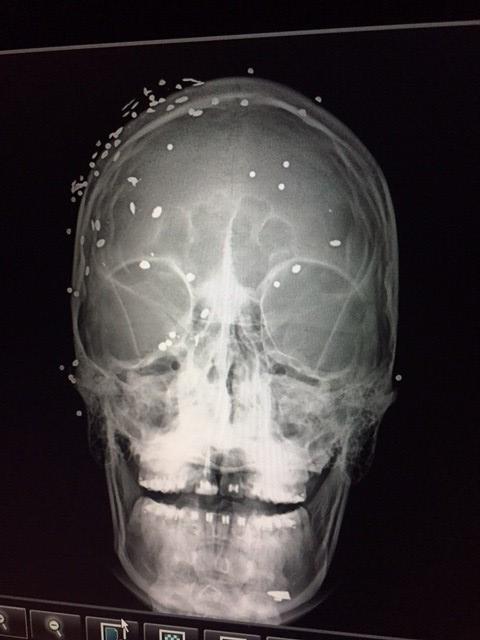

X-ray of patient injured during an anti-government demonstration in Caracas shows many pellet shots to the face and head, June 2017. © 2017 Private

X-ray of patient injured during an anti-government demonstration in Caracas shows many pellet shots to the face and head, June 2017. © 2017 Private